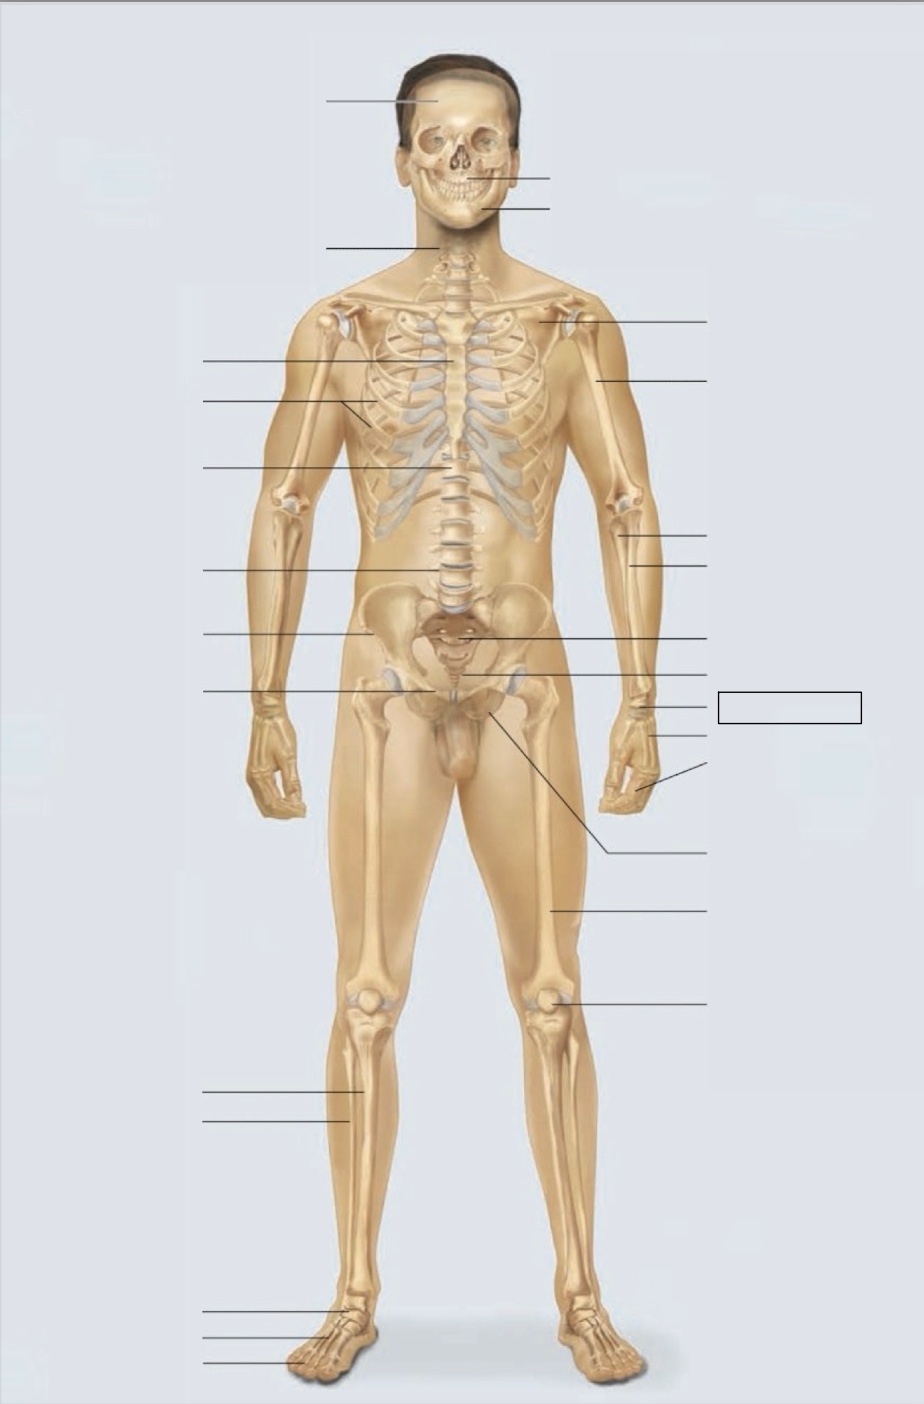

maxilla

mandible

scapula

humerus

ulna

radius

sacrum

coccyx

carpals

metacarpals

phalanges

ischium

femur

patella

phalanges

metatarsals

tarsals

fibula

tibia

pubis

ilium

lumbar vertebrae (L4)

thoracic vertebrae (T11)

ribs

sternum

cervical vertebrae

skull